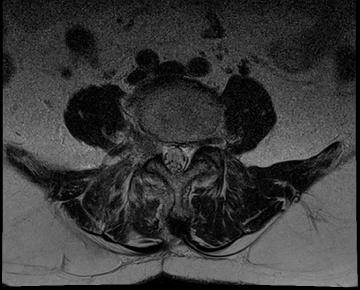

요추 협착증 수술 전·후

2020.08.30

2022.09.06

ㆍ환자 동의를 받은 자료이며, 이미지 사진은 실물과 다를 수 있습니다.

ㆍ모든 자료는 새움병원 자료입니다.